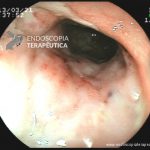

- Doença de Crohn em remissão – cicatriz